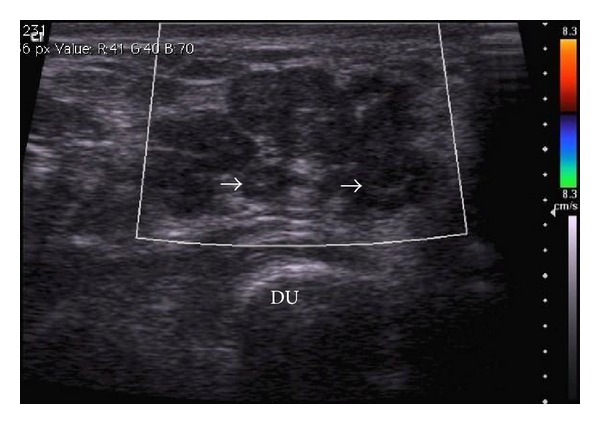

Figure 4.

Ultrasound of the wrist—conglomerate multilobulated lesions with target appearance (white arrows): central hyperechogenicity with hypoechoic periphery. No vascularity noted on colour Doppler. DU: distal ulna.